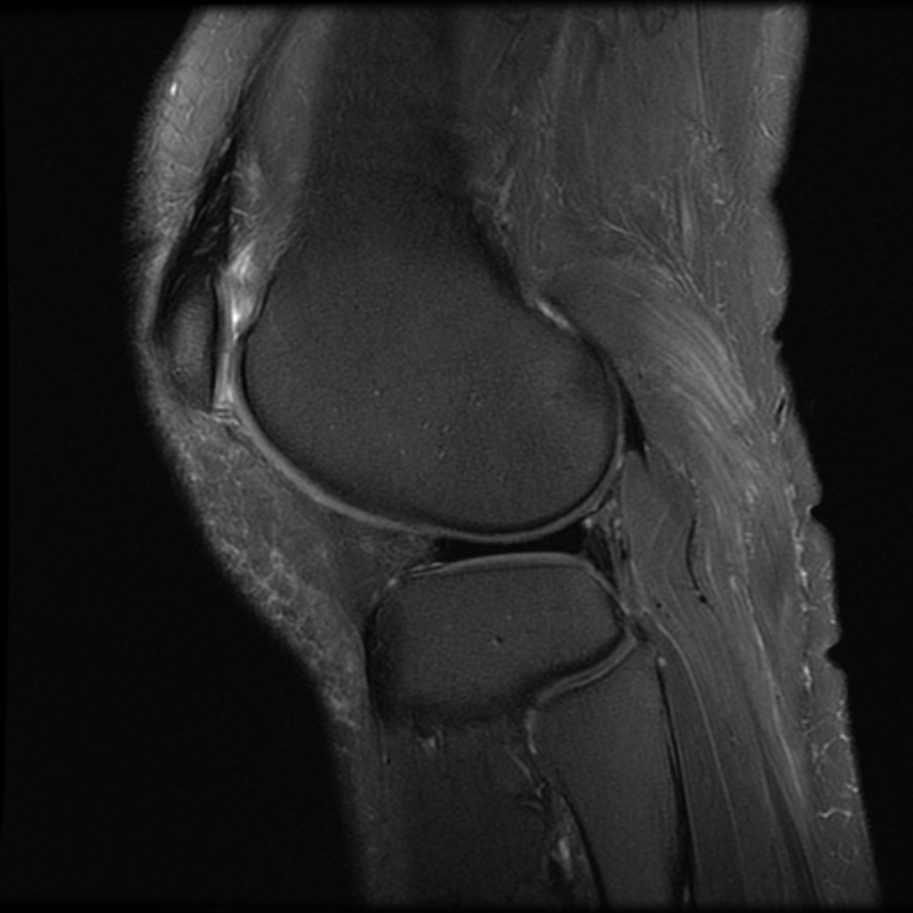

以上是直方图均衡Histogram Equalization的简单应用。事实上,HE最初用在医疗图像上。以下图为例:

如果只应用简单的HE,结果如图:

尽管组织“点亮”了,但底噪一样被“点亮”了。

MATLAB内置了adapthisteq函数,可以实现CLAHE算法。我们以Human Knee为例,看看CLAHE效果:

不仅目标被点亮了,而且低噪也被抑制了!